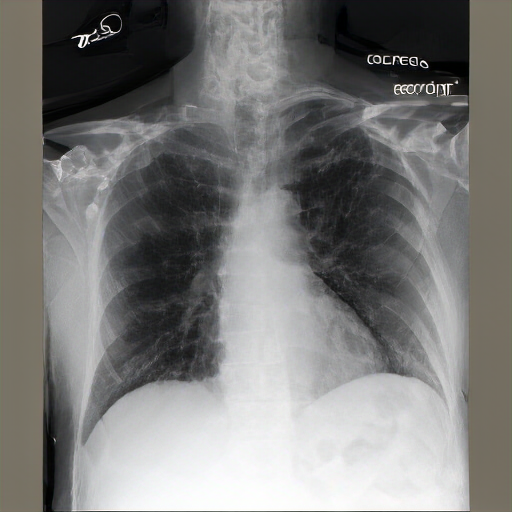

The image is a radiograph of the chest, showing the thoracic cavity structures. Multibibasilar opacities could represent overlap of the apex. No clinical evidence for pneumonia. There are new bilateral infrahilar infiltrates and mild pulmonary edema with flattening of the diaphragmatic contour.